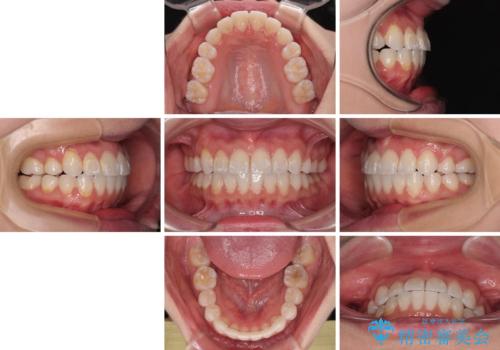

- 八重歯と、それによる正中のズレを気にして来院された患者様です。

口元の突出感は気にしていなかったため、上顎の左右第一小臼歯を抜歯することで、八重歯の解消と上顎の正中を改善していくこととしました。

奥歯の咬み合わせを維持しながら正中位置を改善するために、補助装置を使用しました。

予定より期間がかかりましたが、上下の正中位置を綺麗に一致させることができました。